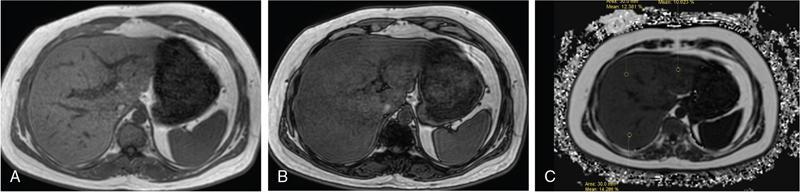

Excessive triglyceride accumulation within hepatocytes is defined as hepatic steatosis. Major conditions associated with hepatic steatosis include alcoholic fatty liver disease (AFLD) and nonalcoholic fatty liver disease (NAFLD). Causes of hepatic steatosis are discussed in Table 9.10.3. NAFLD is the most common form of hepatic steatosis and discussed in detail below. Up to 90% of patients with chronic alcoholic intake have fatty liver. Those with pure AFLD have a 10% risk of progressing to cirrhosis. Consumption of 30 g ethanol/day shows increased risk of chronic liver disease and cirrhosis. Other risk factors include female sex, obesity, cigarette smoking, obesity and associated risk factors. These factors are divided into 2 main categories which can cause fatty liver: inborn errors of metabolism and acquired metabolic disorders. Inborn errors of metabolism include abetalipoproteinemia, galactosemia, glycogen storage disease, hereditary fructose intolerance, homocystinuria and Wilson disease. Inflammatory bowel disease, jejunoileal bypass, malnutrition, starvation and total parenteral nutrition are acquired metabolic factors associated with increased risk. Chronic HCV infection, is associated with hepatic steatosis, with prevalence of 40%–80%. Hepatic steatosis can be seen as an adverse reaction to some medications such as tetracycline, valproic acid, some of chemotherapeutic agents, dexamethasone, amiodarone, methotrexate, tamoxifen and acetylsalicylic acid. Either microvesicular or macrovesicular steatosis can be observed in drug-induced hepatic steatosis. It generally occurs with therapy lasting several weeks or months and is reversible after discontinuation. The leading cause of hepatic steatosis in paediatric population is NAFLD. Six per cent of these patients develop cirrhosis and end-stage disease. Other less common causes include starvation and malnutrition, drugs (glucocorticoids, oestrogens, tetracyclines, and methotrexate), intoxications (carbon tetrachloride, organic phosphates, organic solvents, and alcohol), metabolic disorders, hepatitis C infection, and total parenteral nutrition. NAFLD is defined as steatosis affecting >5% of hepatocytes in the absence of a secondary cause. NAFLD represents a spectrum of disease, ranging from simple steatosis to steatohepatitis through to fibrosis and cirrhosis and in some cases hepatocellular carcinoma. NAFLD is a growing epidemic worldwide in part due to obesity and insulin resistance leading to liver accumulation of triglycerides and free fatty acids. Nonalcoholic steatohepatitis (NASH) is defined by histologic terms as a necroinflammatory process whereby the liver cells become injured in a background of steatosis. 20% of patients with NAFL progress to NASH, which progresses to fibrosis and cirrhosis over a 15-year time period (Fig. 9.10.3). The definition of NAFLD requires imaging or histology evidence of steatosis and no causes for secondary hepatic fat accumulation like significant alcohol intake, drugs or hereditary disorders (Table 9.10.4). The incidence of NAFLD ranges from 20% to 30% in Western countries and 5%–18% in Asia. As it currently stands, NAFLD represents the second most common reason to be listed for a liver transplant. The prevalence of NAFLD is higher in patients with obesity, diabetes, and patients with hyperlipidaemia. Prevalence increase with age from less than 20% at age 20 to more than 40% over 60 years of age. Males show a higher risk for progression to NASH and fibrosis (Table 9.10.5). Up to 90% of patients with NAFLD have simple steatosis, and about 30% of patients with NAFL develop NASH, and in again about 30%–40% of NASH patients the disease progresses to manifest fibrosis and cirrhosis NAFLD related cirrhosis has a 10-year mortality of 25% and a 5% chance of developing end-stage liver disease and HCC. The theory implicated in the pathogenesis of NAFLD is the two-hit theory. Insulin resistance, enhanced dietary influx and increased hepatic lipogenesis leading to accumulation of triglycerides (TG) and FFA in the hepatocytes is the first hit. The lipid peroxidation, mitochondrial dysfunction and inflammation resulting in hepatocyte damage and development of liver fibrosis is the second hit. The stages of NAFLD on histology range from steatosis initially to hepatic fibrosis in late stages. In the steatotic stage large (macro-) and small (micro-) vesicles of fat, predominately triglycerides, accumulate within hepatocytes. The affected parenchyma is divided into thirds: 5%–33%, 34%–66% and >66% and graded as mild, moderate and respectively. Ballooned hepatocytes with accompanied steatosis and inflammation are characteristic of the steatohepatitis stage. Fibrosis has a characteristic appearance with early lesions showing a perisinusoidal deposition followed by periportal fibrosis which progresses to bridging. Raised GGT is the most common liver enzyme elevated in NAFLD. Transaminases are within normal range in 80% patients. No specific blood tests can diagnose NAFLD. Liver biopsy has remained the gold standard for diagnosis and quantification of liver fat. Drawbacks, however, include invasive nature, sampling error and procedure related complications like bleeding. Various imaging techniques are currently available in diagnosing and quantifying liver fat. MRI in particular proton density imaging and MR Spectroscopy have revolutionized imaging of fatty liver. Normal liver parenchyma is the same as or slightly more echogenic than the adjacent kidney and spleen. Fat deposition leads to increased echogenicity of liver. Decreased beam attenuation in patients with fatty change leads to poor visualization of structures such as intrahepatic vessels, bile ducts and liver lesions and in severe cases diaphragm (Table 9.10.6). Fatty liver can be graded on USG as: US has a fair accuracy of detecting the moderate to severe hepatic steatosis with sensitivity of about 90% and specificity of about 95% for patients without concomitant chronic liver disease. Ultrasound is observer and equipment dependent. Confounding factors such as large body hiatus may lead to overestimation of hepatic steatosis due to beam attenuation by overlying fat. Conditions like fibrosis, inflammation can affect interpretation. The ratio between the mean brightness level of liver and right kidney is called the Hepatorenal sonographic index. A cut off of 1.49 has a high sensitivity and specificity for diagnosis of steatosis >5%. The main advantages of CT for assessing steatosis are relatively fast acquisition, ease of performance, and quantitative results. Estimation of fatty liver is done on non-contrast enhanced images. The normal liver density is around 60 HU, which is approximately 10 HU higher than normal spleen. Fat accumulation in the liver manifests as proportionate decrease in density. Both the absolute and relative (to the spleen) values are used to characterize steatosis; a cut-off value of 40 HU has been suggested to predict fat content greater than 30% (Figs. 9.10.6 and 9.10.7) Attenuation difference between liver and spleen on unenhanced CT scan is a commonly used quantitative parameter to evaluate hepatic steatosis. This avoids errors in attenuation value measurement from different CT scanners and different reconstruction algorithms. Normal liver parenchymal attenuation on nonenhanced CT is slightly higher than the spleen. Liver attenuation progressively decreases as percentage steatosis increases (Table 9.10.7) (Fig. 9.10.8) Methods of liver fat quantification on CT have been discussed in details in chapter on liver transplant. Limited diagnostic accuracy for detecting mild degree hepatic steatosis is one of major drawback of CT. Disorders causing hyperdensity of liver such as iron, glycogen deposition can lead to errors in interpretation. The concomitant presence of iron and fat may not be accurately diagnosed on CT. Low CT density values may also be caused by oedema and inflammation. Likewise, the spleen is an imperfect reference standard as it can be affected by haemosiderosis and haemochromatosis in a small minority of patients. Dual-energy CT with its ability to perform material decomposition is more accurate in quantifying hepatic steatosis and allows staging of fibrosis. Imaging is done with two different energies (typically 80 kVp and 140 kVp). DECT has the potential to quantitate liver fat content independent of ROI (region of interest) placement. Magnetic resonance imaging (MRI) is presently the most accurate imaging modality for the evaluation of hepatic steatosis. Several different methods have been developed and introduced in MRI for the evaluation of hepatic steatosis. In this technique typically, two gradient echoes are acquired, one employing a TE in which the water peak (4.7 ppm) and the dominant fat peak (1.3 ppm) are ‘out of phase’ and hence subtractive (SOP), and the other using a TE in which the two peaks are ‘in phase’ and therefore additive (SIP). Because two echoes are acquired, this is often called ‘dual-phase’ or ‘dual echo’ imaging. Fat Signal Percentage is calculated as [SIP – SOP]/[2 × SIP] ×100. The dynamic range of magnitude based chemical shift techniques has typically a 0%–50% signal fat-fraction (Fig. 9.10.9) This technique uses both magnitude and phase information from three or more images acquired at different echo times appropriate for more accurate separation of water and fat signals as against only magnitude information in dual-echo. These methods provide estimates of fat fraction with a dynamic range of 0%–100%. Proton density Fat fraction (PDFF) is calculated as Sf/(Sw + Sf) where Sw = SI of the water component, Sf = SI of the fat component. PDFF specifically reflects the concentration of triglycerides in the hepatocytes as lipids within the other structures such as cell membranes and organelles are occult. Sensitivity up to 96% and specificity up to 100% for detecting any degree of steatosis have been reported. A fat-fraction threshold of 5.56% is commonly used to define steatosis; however, the optimal cut-off value still needs to be defined (Figs. 9.10.10 and 9.10.11). MRS can directly measure the chemical composition within tissue based on the frequency composition of the signal originated from the voxel of interest. Water proton peak appears as a single peak at 4.7 ppm, whereas fat peaks appear as multiple peaks around 1.3 ppm. PDFF can be calculated as the ratio of the sum of the signal intensities derived from the protons in fat divided by the sum of the signal intensities originated from the protons in both fat and water (Fig. 9.10.12). TABLE 9.10.8 MRS data are usually obtained from a single voxel manually placed in the liver parenchyma usually right posterior segment of the liver. Reported MRS sensitivities and specificities for detection of mild hepatic steatosis are 80.0%–91.0% and 80.2%–87.0%, respectively, outperforming CT and US. MRS can also provide excellent reproducibility of measurement. It is also unaffected by confounding factors like fibrosis, iron overload and glycogen. Small sample volume usually less than 3 × 3 × 3 cm3 is a major limitation of MRS, particularly in patients with uneven fatty change. Despite these practical limitations, MRS is considered to be the gold standard MR method for hepatic fat quantification. This is the most frequently encountered pattern and considering the homogenous involvement poses no diagnostic dilemma. Focal fat deposition and focal sparing in diffuse fatty liver are less common. These usually occur in specific locations like adjacent to falciform ligament or ligamentum venosum, in portal hepatis or gallbladder fossa. Imaging findings are suggestive of fatty pseudolesions rather than true masses. Occurrence in characteristic locations, absence of mass effect on vessels and structures, geographic configuration and contrast enhancement similar to or less than adjacent liver (Fig. 9.10.13). Fat deposition around insulinoma metastasis can occur as a local effect of insulin on the liver parenchyma. On ultrasound, it appears as an echogenic rim shows signal drop on out of phase images. Eisenberg has reported perilesional steatosis around focal nodular hyperplasia. Sometimes multiple small foci and seen scattered throughout the liver. These may appear as small round nodules (Fig. 9.10.14). Opposed phased imaging is more useful than CT or US to establish diagnosis. These may, however, pose a diagnostic dilemma in patients with known malignancy. Perivascular fatty infiltration is a recently described entity, mostly seen in alcoholic patients. This pattern is characterized by halos of fat that surround the hepatic veins, the portal veins, or both hepatic and portal veins (Fig. 9.10.15). Normal vessels coursing through the lesion without attenuation in calibre suggest the diagnosis. Peritoneal dialysis with insulin in the dialysate in patients with renal failure and insulin-dependent diabetes. Exposure of subcapsular hepatocytes to a higher concentration of insulin results in fat deposition in the subcapsular regions. Some hepatic lesions such as hepatic adenoma, hepatocellular carcinoma, regenerative nodules and focal nodular hyperplasia can show intracellular steatosis (Fig. 9.10.16). These areas show signal drop on opposed phase. However, postcontrast imaging characteristics of these lesions allow differentiation from areas of focal steatosis. Perilesional sparing has been reported in haemangioma and hepatocellular carcinomas. This may mainly represent decreased portal flow due to either compressed or atrophic hepatocyte cords in expanding metastases or arterioportal perfusion abnormalities in haemangiomas. The differential diagnosis of focal fat infiltration is discussed in Table 9.10.9. Accurate history and chemical shift imaging showing signal drop help in differentiation of focal fat from metastasis. These are visible only during the arterial and portal venous phases after contrast agent administration. The morphologic appearance of fat deposition and perfusion abnormalities is similar. Perfusion abnormalities however are visible only during the arterial and portal venous phases (Fig. 9.10.17). They are not seen as an attenuation difference on nonenhanced CT. Periportal oedema, inflammation, haemorrhage and lymphatic dilatation may mimic perivascular fat. With the exception of haemorrhage all other conditions affect periportal region symmetrically (Fig. 9.10.18). Patients with haemorrhages may show other signs of injury. Chemical shift imaging is helpful in cases with diagnostic challenges.

Chemical shift imaging (dual echo)

Multi-echo dixon sequences

MRS